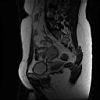

Abdomen